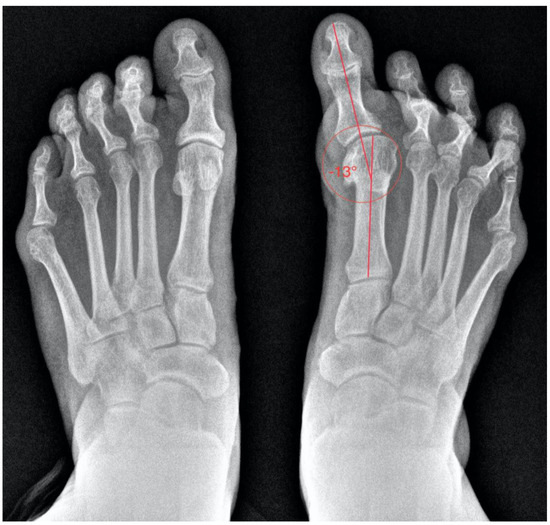

The postoperative radiological (Figure 4) study showed the correct alignment of all the toes. A good evolution of the resection of metatarsal heads and an asymptomatic non-union of the first MTP joint was observed.

Figure 4. Image of the foot in load after 48 months.